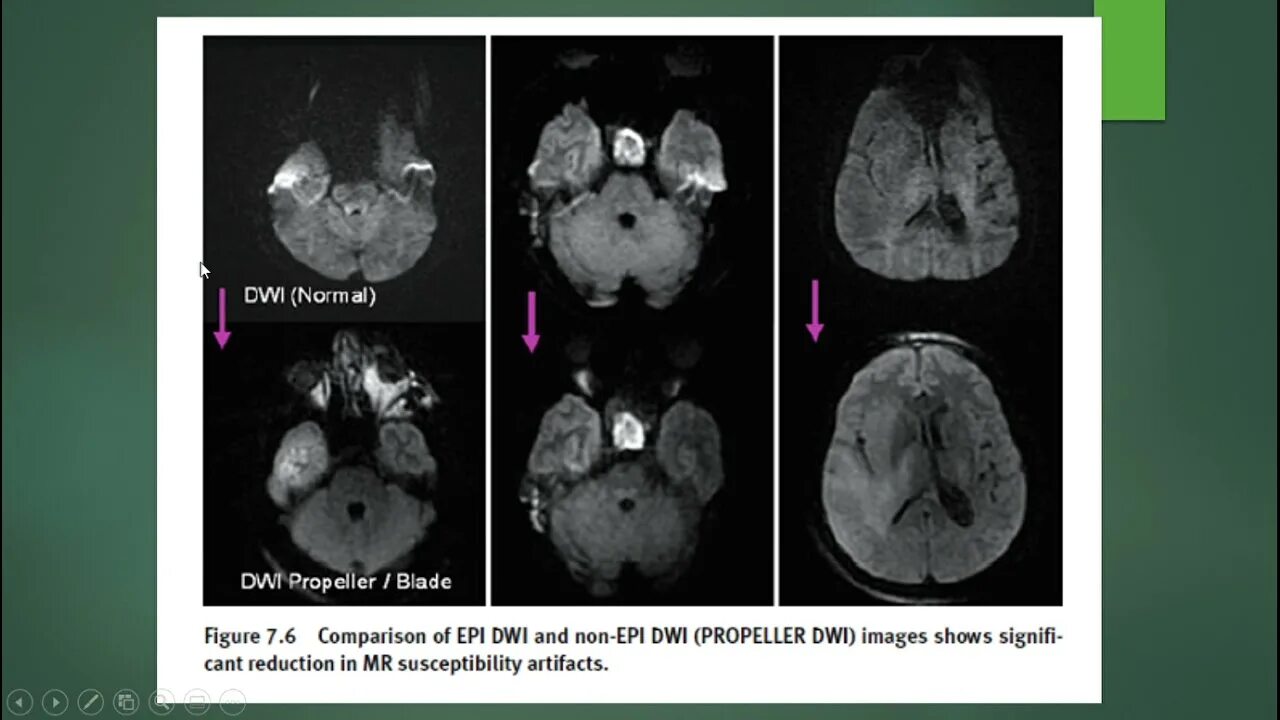

Мрт височных костей в режиме dwi